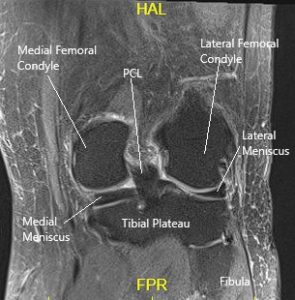

MRI of the left knee suggested a medial meniscal tear and medial and patellofemoral compartment articular cartilage defects.